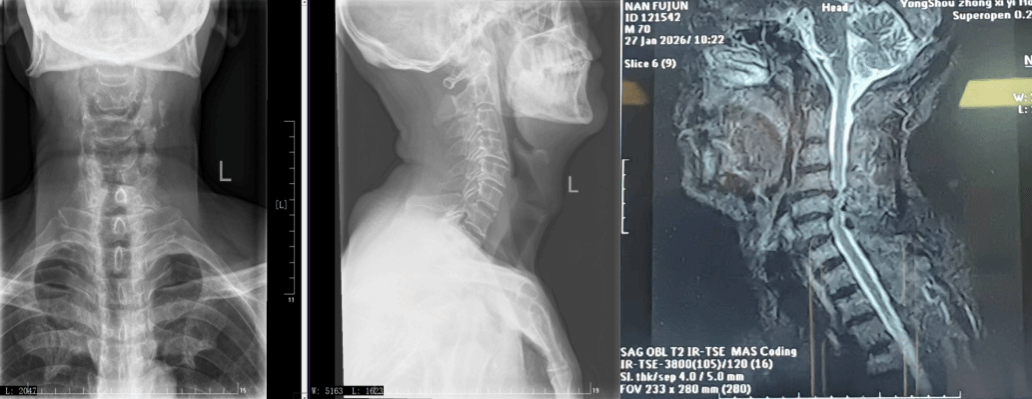

影像现形:两节椎间盘同时“出轨”

入院后的影像学检查很快揪出了病因——南大爷的颈4-5、颈5-6两节颈椎间盘同时突出,像两块错位的软垫,死死顶住了后方的脊髓和神经根。更棘手的是,椎体已经出现不稳,保守治疗根本无力回天。